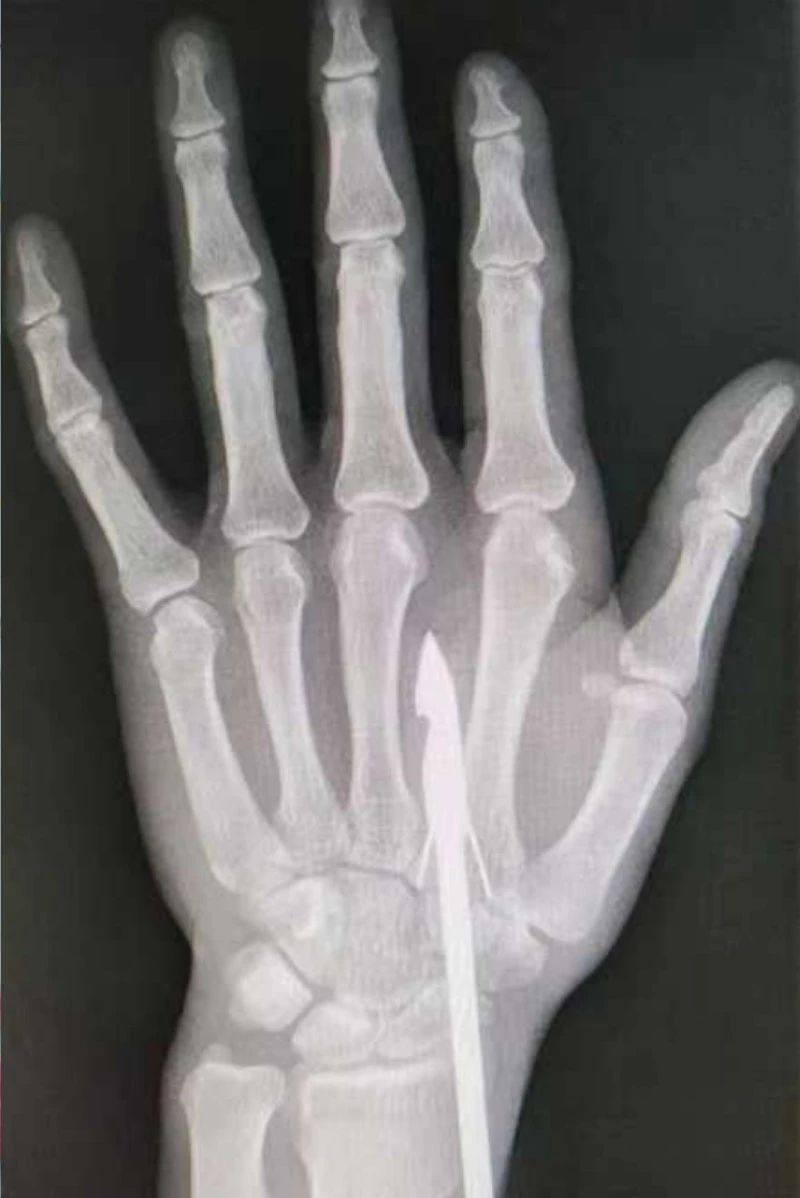

時間緊迫,每一秒的流逝都可能對傷者的手部功能造成不可逆的損害。接診醫(yī)生代彭威,迅速對傷者進(jìn)行了初步檢查。他注意到,魚鉤已經(jīng)深深嵌入皮膚,情況遠(yuǎn)比表面看起來復(fù)雜。沒有絲毫猶豫,立即安排了X線檢查以確認(rèn)魚鉤的位置及傷及范圍,以及急診化驗(yàn)檢查以評估患者的整體狀況。

確保在取出魚鉤的同時,不對周圍的組織造成額外的傷害。8點(diǎn)15分左右患者在局部浸潤麻下進(jìn)行手術(shù),經(jīng)探查后魚鉤未傷及重要血管、神經(jīng)及肌腱,經(jīng)過緊張的十分鐘,魚鉤終于被順利取出,隨后對傷口進(jìn)行了仔細(xì)的清理和縫合,用敷料仔細(xì)包扎,確保傷口能夠順利愈合。